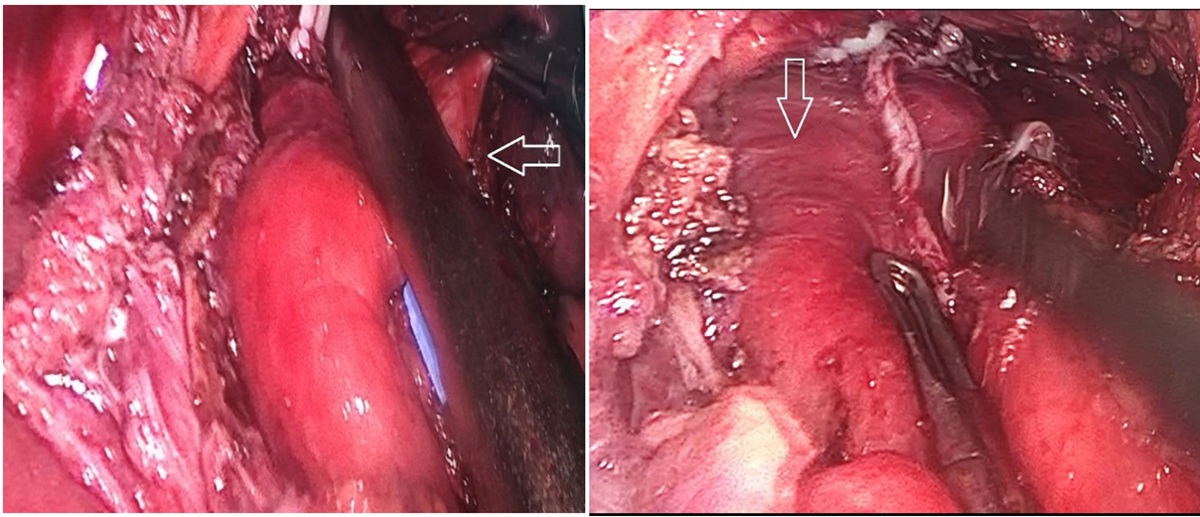

Bệnh nhân được chỉ định phẫu thuật nội soi cắt túi thừa thực quản kèm điều trị trào ngược dạ dày thực quản. Phương pháp vô cảm: Mê nội khí quản. Tiến hành cắt túi thừa, chống trào ngược bằng phương pháp Dor. Phẫu tích cắt dọc tới cổ túi chỗ nối thực quản dạ dày có động mạch đường kính khoảng 3mm chạy ngang đè vào ống niêm mạc ngang vùng cổ túi thừa, xử trí cắt động mạch. Thời gian cuộc mổ khoảng 4 giờ, lượng máu mất khoảng 20ml. Không ghi nhận tai biến trong lúc mổ.

Hình 2: Túi thừa thực quản được cắt bằng Echelon 60 ngang cổ túi

Trường hợp bệnh nhân của chúng tôi với những triệu chứng điển hình về lâm sàng, đã được điều trị nội khoa bảo tồn với thuốc ức chế bơm proton nhưng triệu chứng không thuyên giảm, kèm hình ảnh túi thoát vị kích thước lớn trên cận lâm sàng như x-quang thực quản – dạ dày, cắt lớp vi tính ngực, thì chỉ định phẫu thuật nội soi cắt túi thừa là hợp lí để tránh những diễn tiễn xấu đã được trình bày ở trên nếu kéo dài không phẫu thuật. Đại thể túi thừa ở bệnh nhân này to, kích thước khoảng 5x6x5 cm, vùng cổ túi thừa ngang bờ dưới có động mạch đường kính khoảng 3mm, chạy ngang đè vào ống niêm mạc thực quản, theo chúng tôi đây có thể là nguyên nhân gây tăng áp lực phía trên. Các biến chứng sau mổ có thể có của phẫu thuật này là chảy máu (1/8 ca), xì rò đường kim bấm của stappler (1/8 ca) theo nghiên cứu của La´szlo´ Andra´si. Tuy nhiên, trên bệnh nhân này chưa ghi nhận biến chứng do phẫu thuật. Tình trạng của bệnh nhân được cải thiện và các triệu chứng trước mổ giảm một cách tự nhiên. Phẫu thuật nội soi cắt túi thừa thực quản là phương pháp đem lại hiệu quả cao, nhằm điều trị triệt để cũng như cải thiện triệu chứng và nâng cao chất lượng cuộc sống cho người bệnh. Tuy nhiên, để có cái nhìn toàn diện cũng như đánh giá chi tiết hơn về lâm sàng, cận lâm sàng, hiệu quả điều trị của phương pháp này cần có những nghiên cứu sâu hơn với số mẫu đủ lớn và thời gian theo dõi đủ dài.